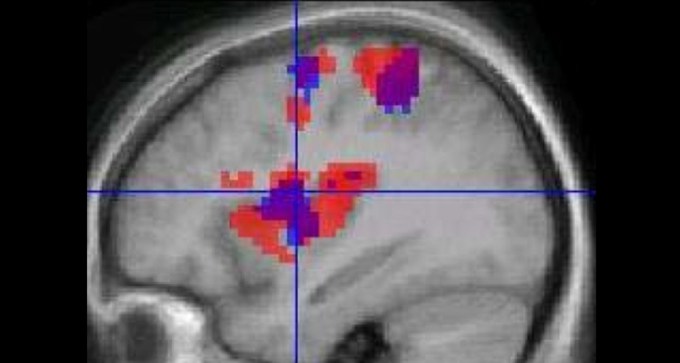

Busy neurons don’t always draw blood

Study of mice suggests caution in inferring the activity of the brain’s neurons from functional MRI results.